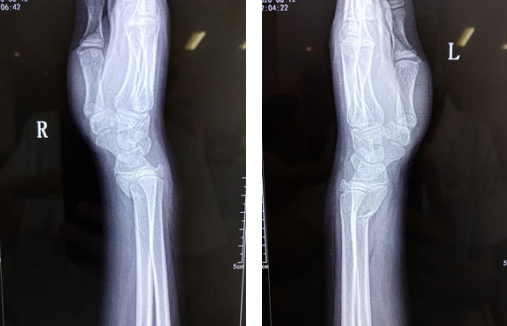

发现孩子双手腕肿胀、畸形后,橙橙的父母立刻带着她去当地医院拍片,发现双桡骨骨折,无法治疗,家人焦急万分,急忙赶往betway在线登陆,经手外科二病区刘桂谦医生诊断:患者双桡骨远端骨折。